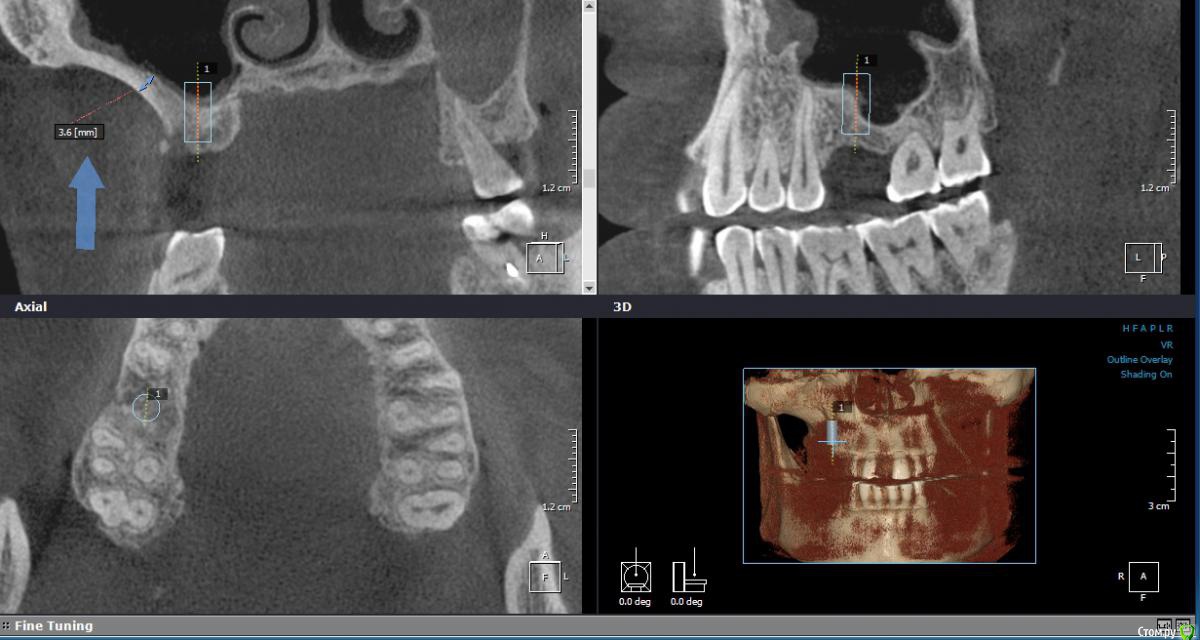

Iv_serg Опубликовано 6 сентября, 2017 Автор Поделиться Опубликовано 6 сентября, 2017 я б закрытый мутил А как закрытый при таком перепаде прямо по центру установки имплантата замутить? В одном месте получается поднимается 1 мм дна, а в другом 4 мм выламывается? Ссылка на комментарий

Iv_serg Опубликовано 8 сентября, 2017 Автор Поделиться Опубликовано 8 сентября, 2017 закрытый тут самое то. В таких толстых стенках надо опасаться прохождения крупного сосуда. Смотрите КТ внимательнее, а так ничего особенного.Сосуд конечно же есть, но вроде некрупный(на первых двух срезах отметил). Еще раз спрошу, как при ЗСЛ работать с таким перепадом(на третьем срезе указал). Ведь фрезой пройти можно до нижнего края, как поднимать кость в области перепада? Ссылка на комментарий

Иван911 Опубликовано 8 сентября, 2017 Поделиться Опубликовано 8 сентября, 2017 (изменено) Сосуд конечно же есть, но вроде некрупный(на первых двух срезах отметил). Еще раз спрошу, как при ЗСЛ работать с таким перепадом(на третьем срезе указал). Ведь фрезой пройти можно до нижнего края, как поднимать кость в области перепада?А если взять на миллиметр ближе к 5, сильно кретично в плане ортопедического положения коронки?, и какой размер импланта на кт вами спроектирован? Изменено 8 сентября, 2017 пользователем Иван911 Ссылка на комментарий